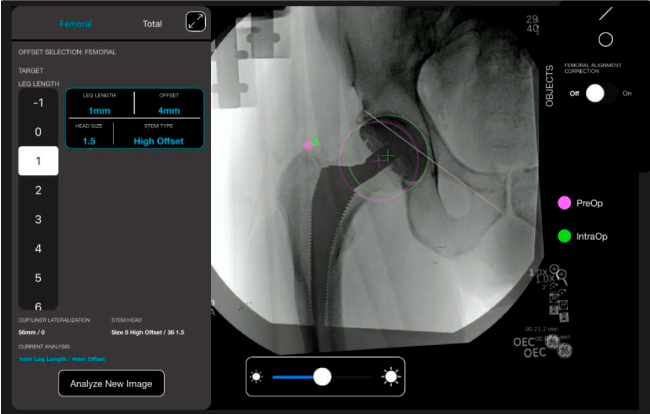

Con tecnología ONETRIAL® que calcula automáticamente el cambio en la longitud de la pierna y el desplazamiento para todas las combinaciones de implantes en una tabla fácil de leer.

Desplazamiento y offset para posicionamiento óptimo del componente (vástago) femoral.

Mayor nivel de información intraoperatoria facilita la colocación correcta de los implantes: